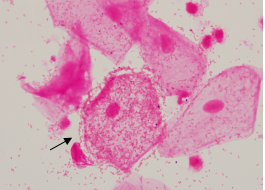

加德纳菌是细菌性阴道病(bacterial vaginosis,BV)的重要病原体,它有一个重要的特点是产生唾液酸苷酶。加德纳菌通过唾液酸苷酶来分解和消耗阴道中含唾液酸的粘液成分,并借此帮助加德纳菌和其他BV致病菌(如普雷沃菌、动弯杆菌、拟杆菌、阴道阿托普菌)粘附在上皮细胞上,加速了BV生物膜的形成。阴道脱落上皮细胞上黏附大量加德纳菌及其他BV致病菌,细胞呈现边缘不整齐、粗糙、透明度不高的形态称为线索细胞(Clue Cell)。